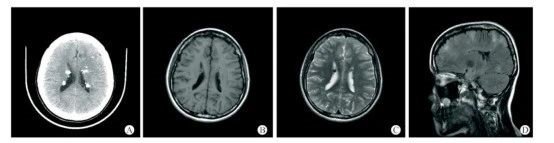

患者臨床表現(xiàn)為癲癇及精神發(fā)育異常,右面部色素沉積斑、四肢及軀干多發(fā)色素脫失斑、雙側(cè)峽部皮脂腺瘤,胸椎多發(fā)斑片狀致密影。A-C:頭顱CT+MRI平掃示雙側(cè)室管膜下及皮層下多發(fā)結(jié)節(jié)樣鈣化灶;D:T2FLAIR示大腦半球皮層及皮層下多發(fā)異常高信號影。